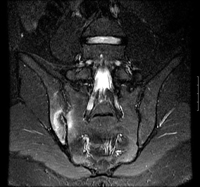

Imagem de ressonância magnética coronal de recuperação de inversão de tau curto STIR (short tau inversion recovery) mostrando sacroileíte unilateral (à direita)

BMJ 2006;333;581-585. © BMJ Publishing Group Ltd 2009